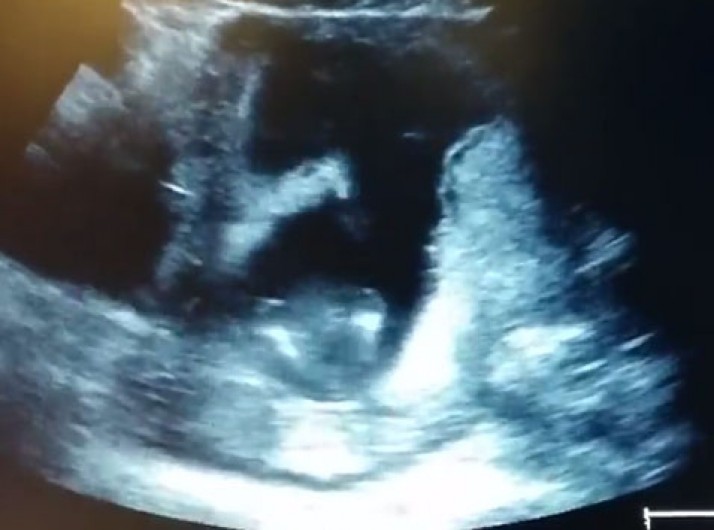

Emocionante: ultrassom mostra feto batendo palmas enquanto mãe canta